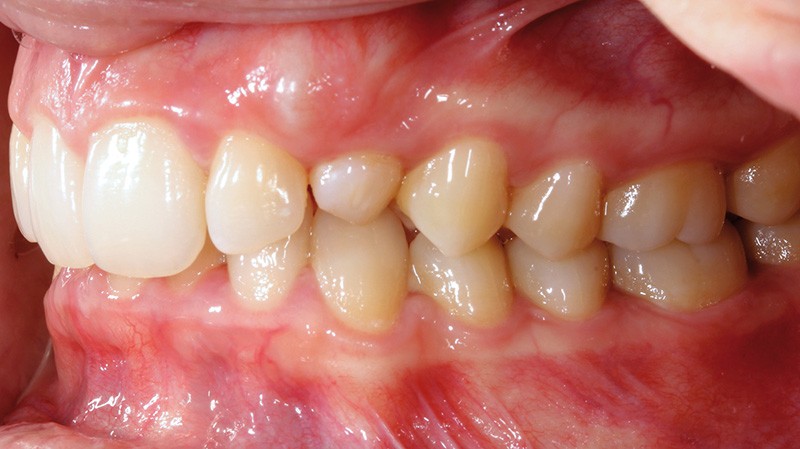

Aline se présente à la consultation pour une demande esthétique concernant ses deux canines lactéales qu’elle trouve trop petites et trop blanches (fig. 1a). Elle présente une classe II squelettique légère sur un schéma méso-divergent. D’un point de vue dentaire, une supraclusion est associée à une classe II d’Angle complète à gauche et de 4 mm à droite. Les canines maxillaires sont incluses (une vestibulaire et une palatine), avec persistance de leurs dents lactéales sur l’arcade (fig. 1b-h).

Un protocole orthodontico-chirurgical avec avancée mandibulaire est envisagé pour assurer un bon soutien labial, mais cette option est refusée par la patiente qui craint un visage trop carré. Concernant l’inclusion des canines maxillaires définitives, plusieurs thérapeutiques sont envisageables : 53, 63, 13, 23, ou 53, 63, 14, 24 peuvent être extraites, avec pour conséquence une classe II thérapeutique au niveau des molaires en fin de traitement. Cependant, la patiente souhaite mettre en place ses canines incluses pour conserver tout son capital dentaire et rétablir un idéal fonctionnel et esthétique au niveau des dents antérieures (fig. 2).